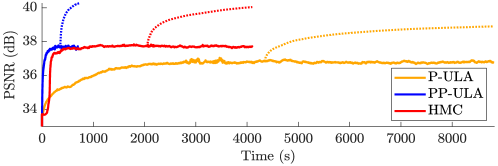

The convergence speed of Algorithm 3 is empirically observed for Simu1 and Simu2, as illustrated in Fig. 2, where we also display the results of the non-preconditioned P-ULA, for which and . Comparing P-ULA and PP-ULA on these simulated data allows us to study the effect of adding a preconditioner in the proposed sampling scheme. As reported in Table II, P-ULA needs more iterations and more time to converge than PP-ULA: the proposed method is 12.2 and 4.8 times faster than P-ULA on Simu1 and Simu2, respectively. In addition, from Table III and Fig. 3, we deduce that P-ULA is more biased than PP-ULA, which samples correctly the target distributions. Finally, as one can see in Fig. 2 and Table IV, P-ULA leads to lower PSNR, SSIM and OA values than PP-ULA. These results clearly emphasize the benefits of preconditioning in this example.

From Table II, PP-ULA is 5.7 and 6.6 times faster than HMC on Simu1 and Simu2 and has better mixing properties, as shown by the MSJ per second. Visual results from Fig. 4 and CNR values in Table IV show that the contrast obtained with PP-ULA is better than with competitors on Simu2, and is second best after P-ULA on Simu1. However, it should be noted that the PSNR and SSIM obtained on Simu1 with P-ULA are much lower than with the other methods. In addition, the PSNR and SSIM values from Table IV obtained with PP-ULA are equivalent or higher than all competitors for these two experiments. Visual segmentation results are shown in Fig. 5, and OA values can be found in Table IV. For these simulated images, more pixels are correctly labeled with PP-ULA than with competitors.